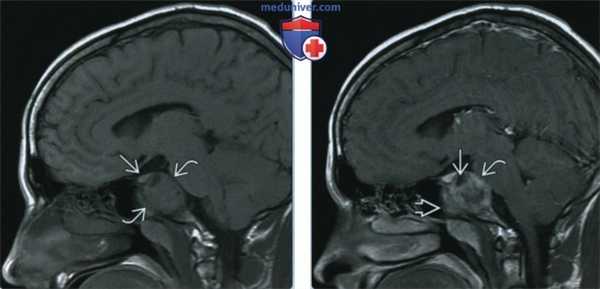

(Слева) При МРТ Т1ВИ в сагиттальной проекции визуализируется распространенная остеосаркома ската затылочной кости, дающая сигнал средней интенсивности. В верхней части опухоли видна неизмененная паренхима гипофиза, что позволяет исключить из дифференциального диагноза инвазивную аденому гипофиза.

(Справа) При МРТ Т1ВИ с КУ в сагиттальной проекции у этого же пациента наблюдается неоднородное контрастирование всей опухоли. Обратите внимание на распространение опухоли в клиновидную пазуху. Неконтрастируемые гипоинтенсивные очаги могут представлять собой зоны остеоида.